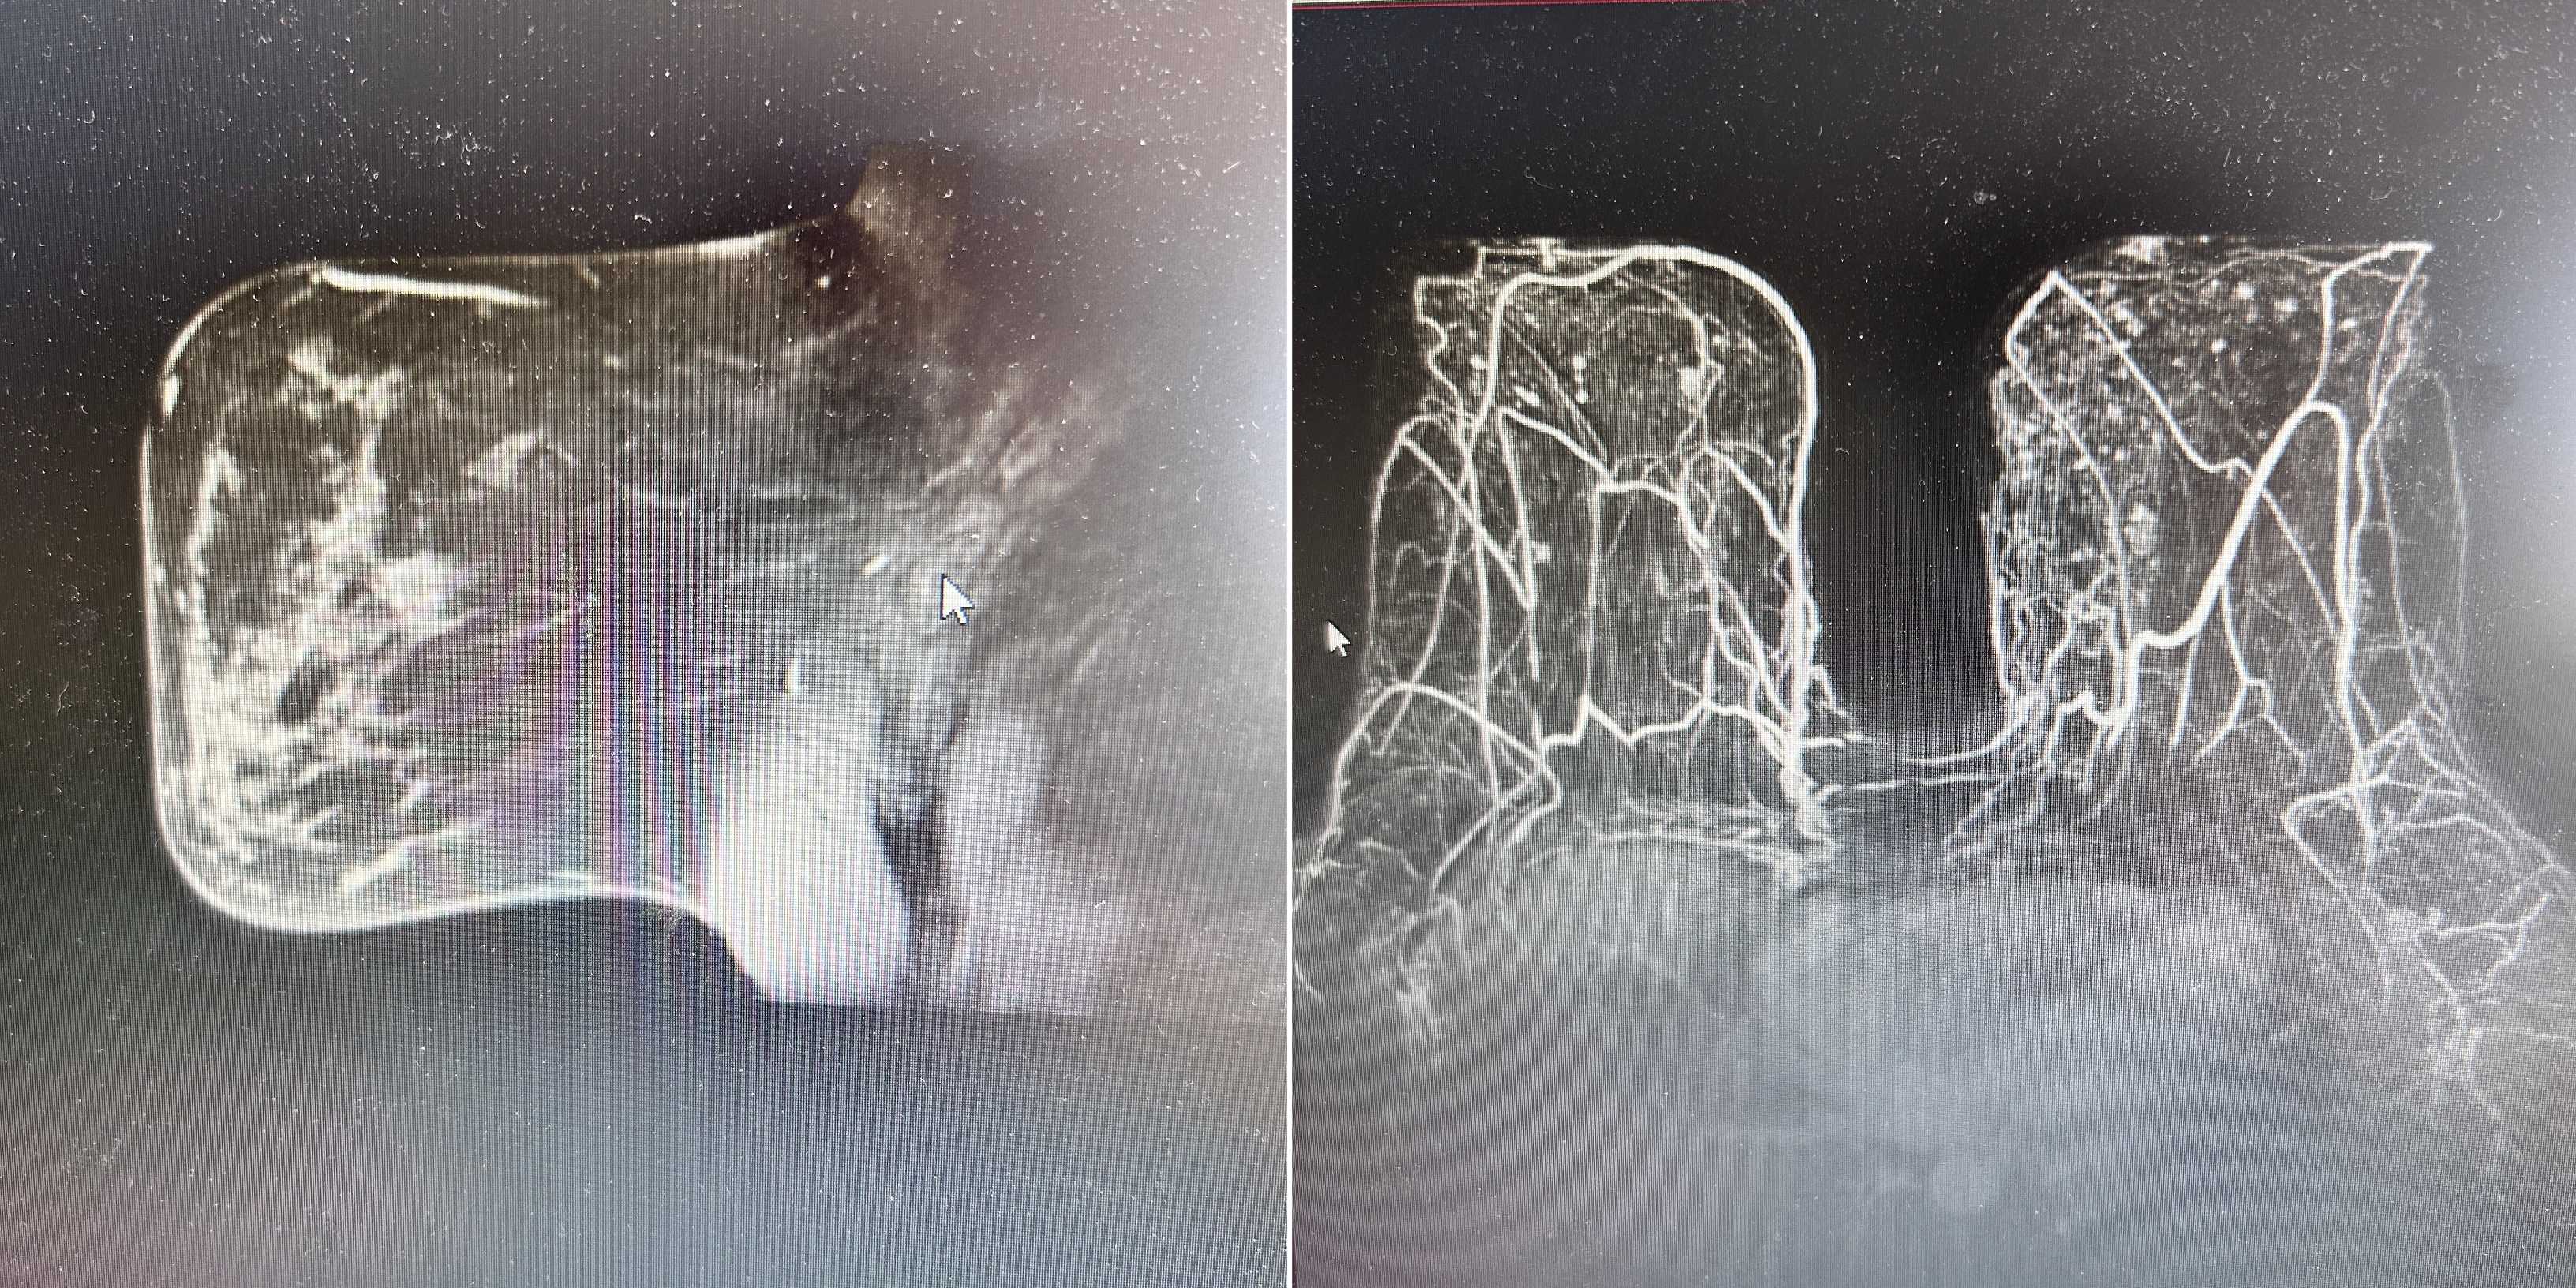

近日,色情导航 乳腺外四科刘克教授团队,运用“双侧保乳联合乳房缩小整形手术”技术,为一名乳腺癌合并巨乳症患者进行个体化治疗,在最大程度保留乳房外形的同时,对肿瘤实施“精准打击”,实现了创伤小、保留美好形态、改善生活质量的目标。

乳腺外四科首席专家刘克教授根据患者的体形等实际情况,多次进行科内会诊,讨论组织切除的范围及位置、切口模式和血液供应等问题,决定为患者行双侧保乳联合乳房缩小整形手术。最终团队在手术麻醉科的配合下,运用专业的手术治疗技术和美学方法,历时4个小时,取得圆满成功,将患者的乳房调至舒适、适宜大小。患者愈后状态良好。